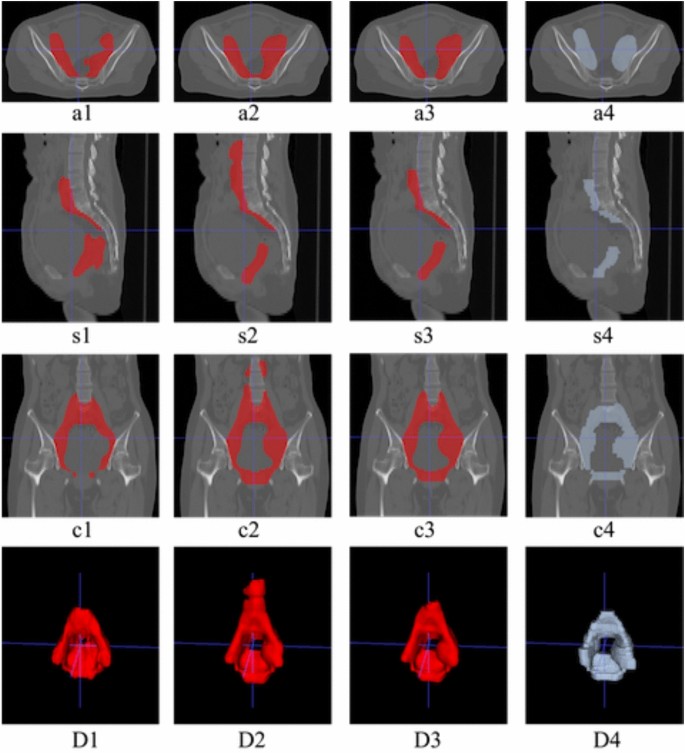

Comparing a1 and a2, s1 and s2, D1 and D2 in Fig. 6, we found that SCN has greatly improved the overall contour segmentation of the backbone, especially the front boundary of CTV. However, there will be some over-segmentation at the upper boundary of CTV, as shown in s2 and c2 in Fig. 6, which also leads to the unsatisfactory Dice of SCN. This may be because the SCN model is used alone without adding the location constraint of OARs, resulting in over-segmentation. WAN can effectively suppress this, as shown in s3 and c3 in Fig. 6. This shows that the addition of the WAN module not only makes the segmentation network perform better in the width direction, as shown in s4 and s5 in Fig. 6, but also is very effective for segmentation in the height direction (a2 vs a3). In general, our ablation study fully demonstrates that the combination of SCN and WAN has better segmentation performance than SCN alone. Besides, we also show the statistical boxes in Fig. 7 to show the effectiveness of our method.

Comparison of backbone, SCN, Our method (SCN+WAN) for segmenting CTV. From top to bottom, axial plane(a), sagittal plane(s), coronal(c), 3D segmentation(D). From left to right, the output results of different models are shown: backbone, SCN, our method (SCN+WAN), and ground truth.